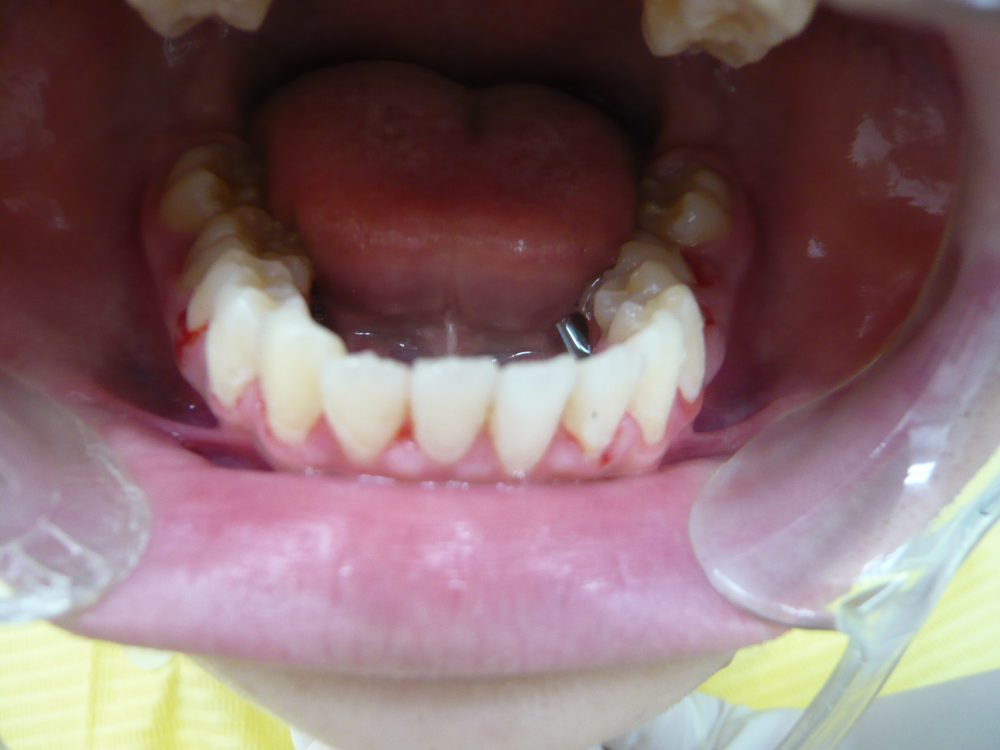

16歳 女性 9か月半

上の前歯が飛び出し、すきっ歯になっています。

ブラケット、ワイヤーで引っ込めました。

後戻り防止のため、就眠中のマウスピースをお願いしています。